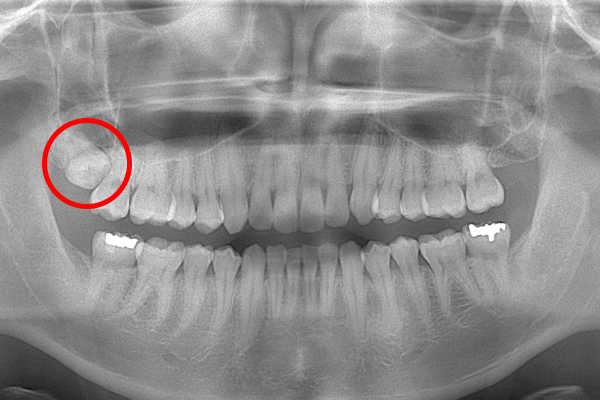

こちらは数年前の私のレントゲン写真です。右上の親知らずが斜めにはえています。お口の中には歯の頭の1部分が見えている状態です。

時々歯茎が腫れて痛かったので、抜いてもらうことにしました。親知らずが上顎洞と接していたため、抜歯後に上顎洞と口腔内が交通しましたが、2週間ほどで塞がりま

ます。